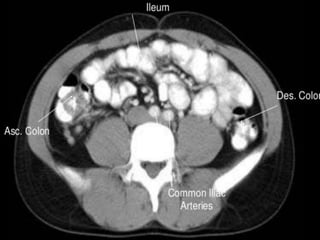

 Jejunum (2.5m)

 Ileum (3.5m)

Extends from jejunum to large intestine

Colon

Ascending colon - on right, between

cecum and right colic flexure

Transverse colon - horizontal portion

Descending colon - left side, between

left colic flexure and

Sigmoid colon - S bend near the

terminal end

• Colon has sacculations

called haustra as teniae coli

are shorter than the colonic

wall

• Colon is relatively peripheral

CT cross sectional

anatomy.